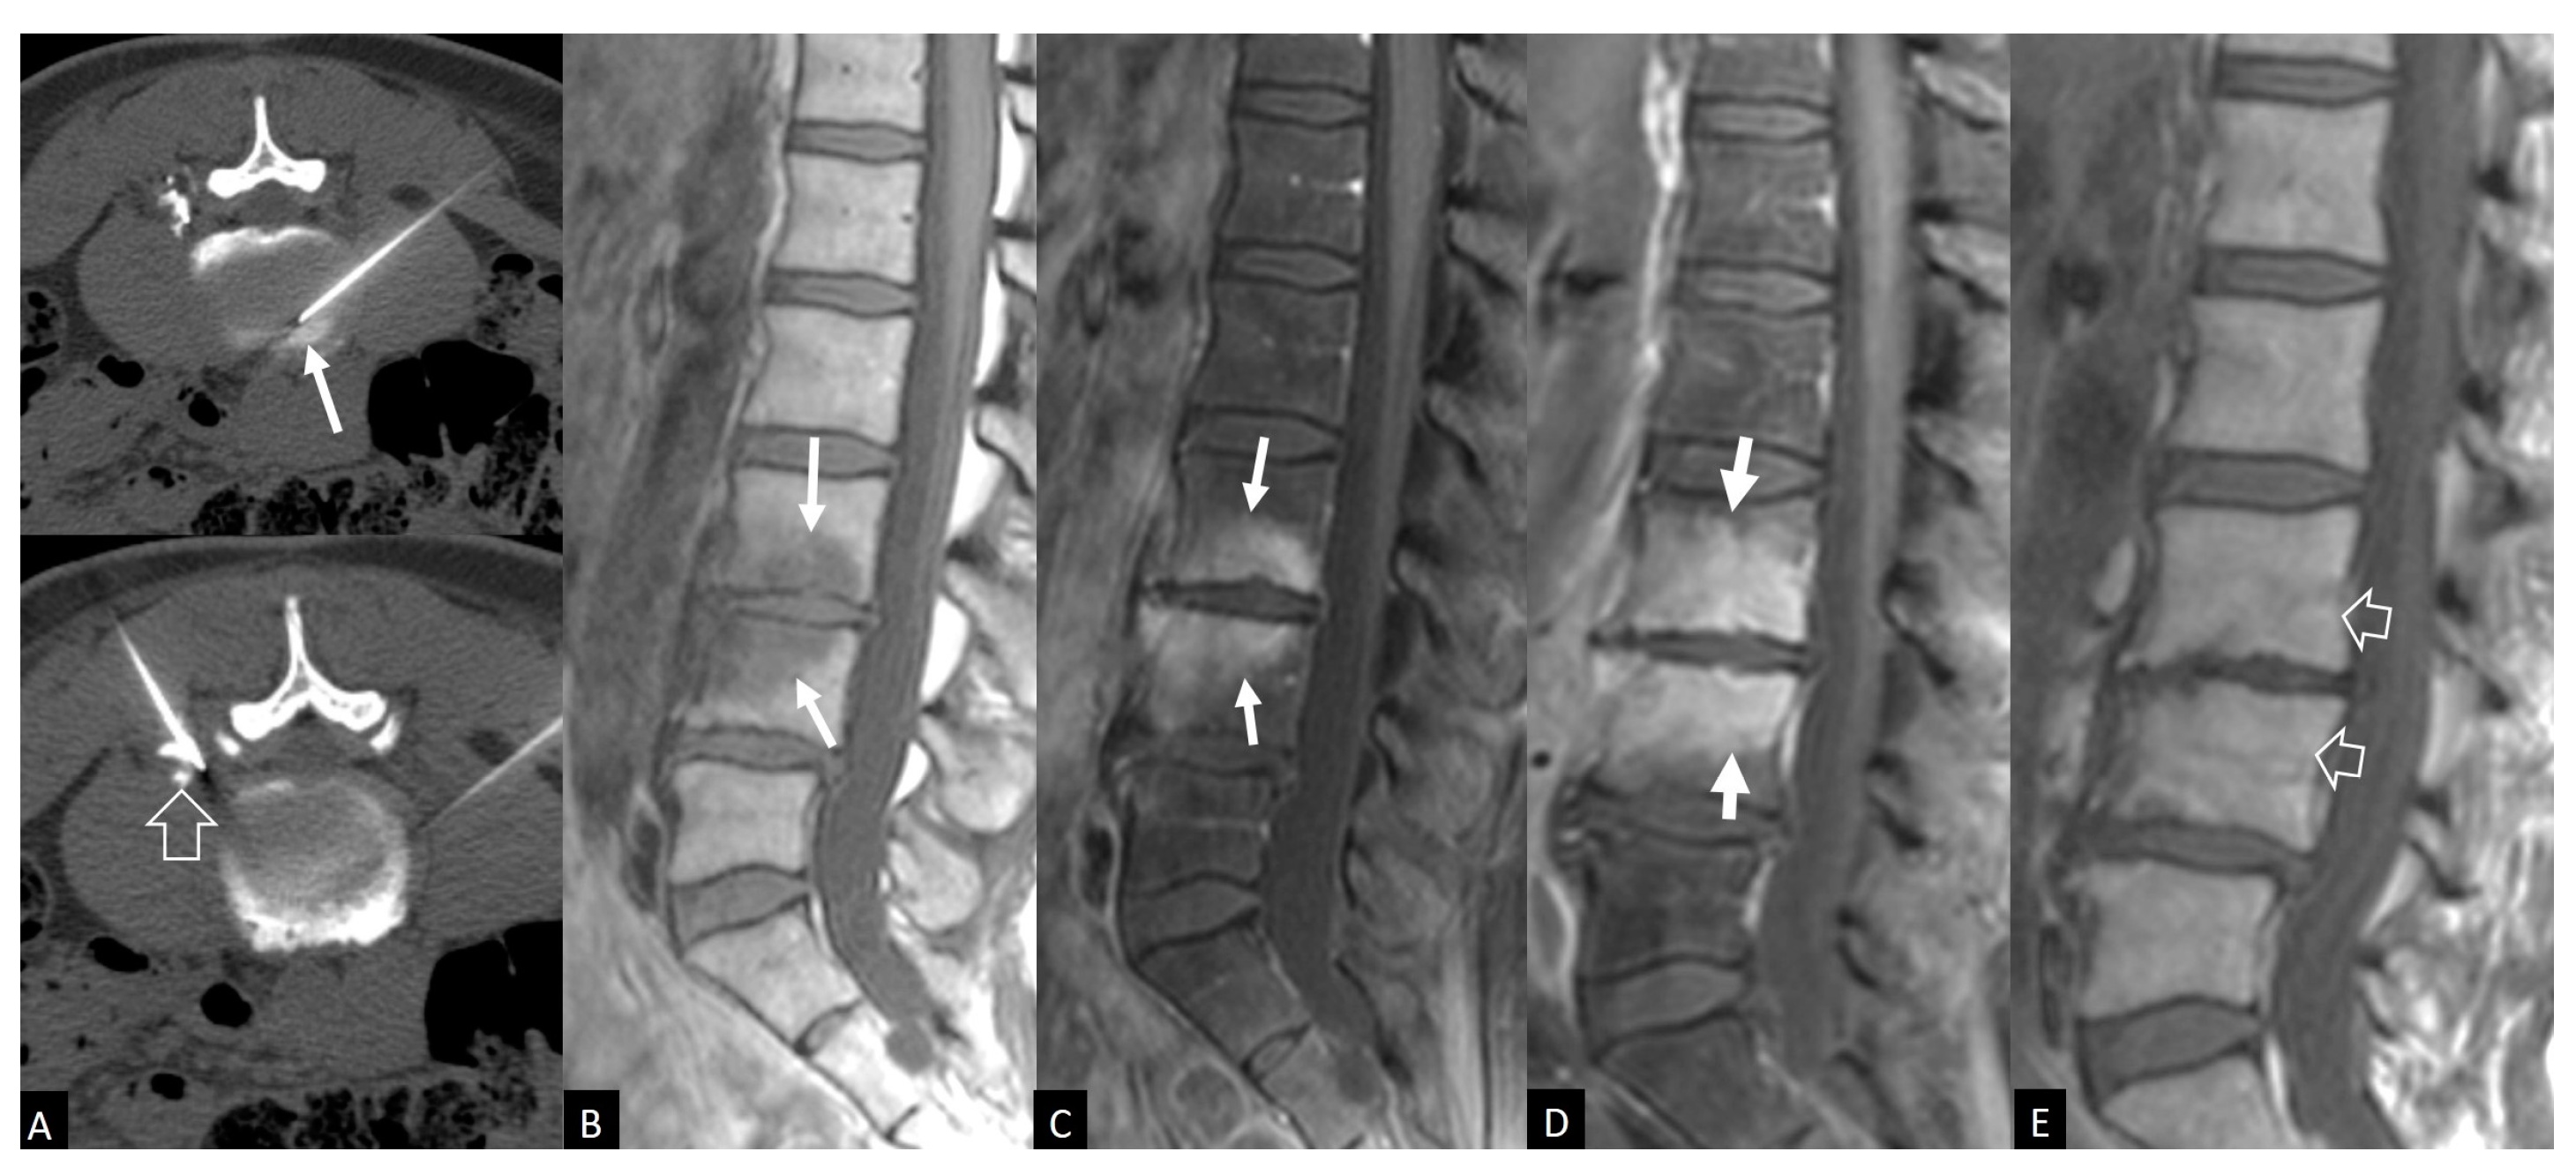

3.4. Imaging